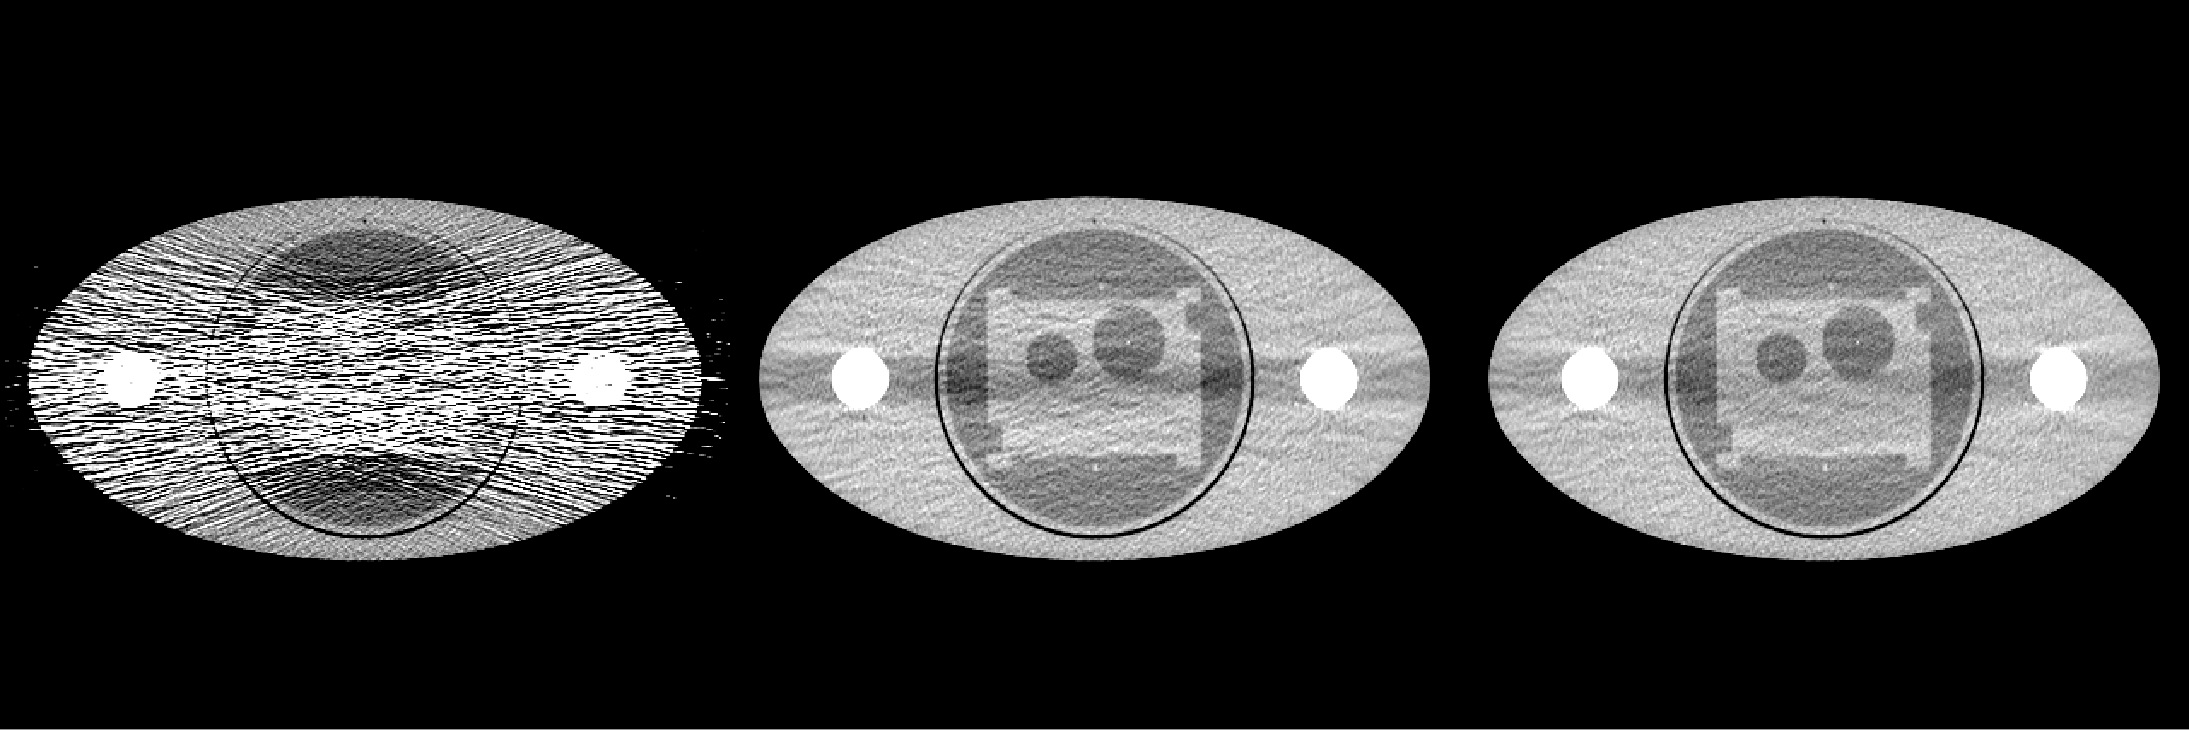

[Uncaptioned image]\captionof

figureRadially averaged profile plot of noise power spectrum in the liver region

MTF measurement was made in a region of interest containing a titanium wire in a low signal phantom. Measurements are rendered for the frequencies at which the response falls to 50%, 10% and 4% of maximum. It can be seen in Table 1 AF LSC receives improved MTF scores at each of these points. The noise power spectrum for AF LSC is flatter than that of FT LSC and uncorrected images, as seen in Fig. 1. This property is typically viewed as advantageous for image evaluation. From the NPS plot it can also be inferred that AF LSC has lower variance in liver region compared to FT LSC.